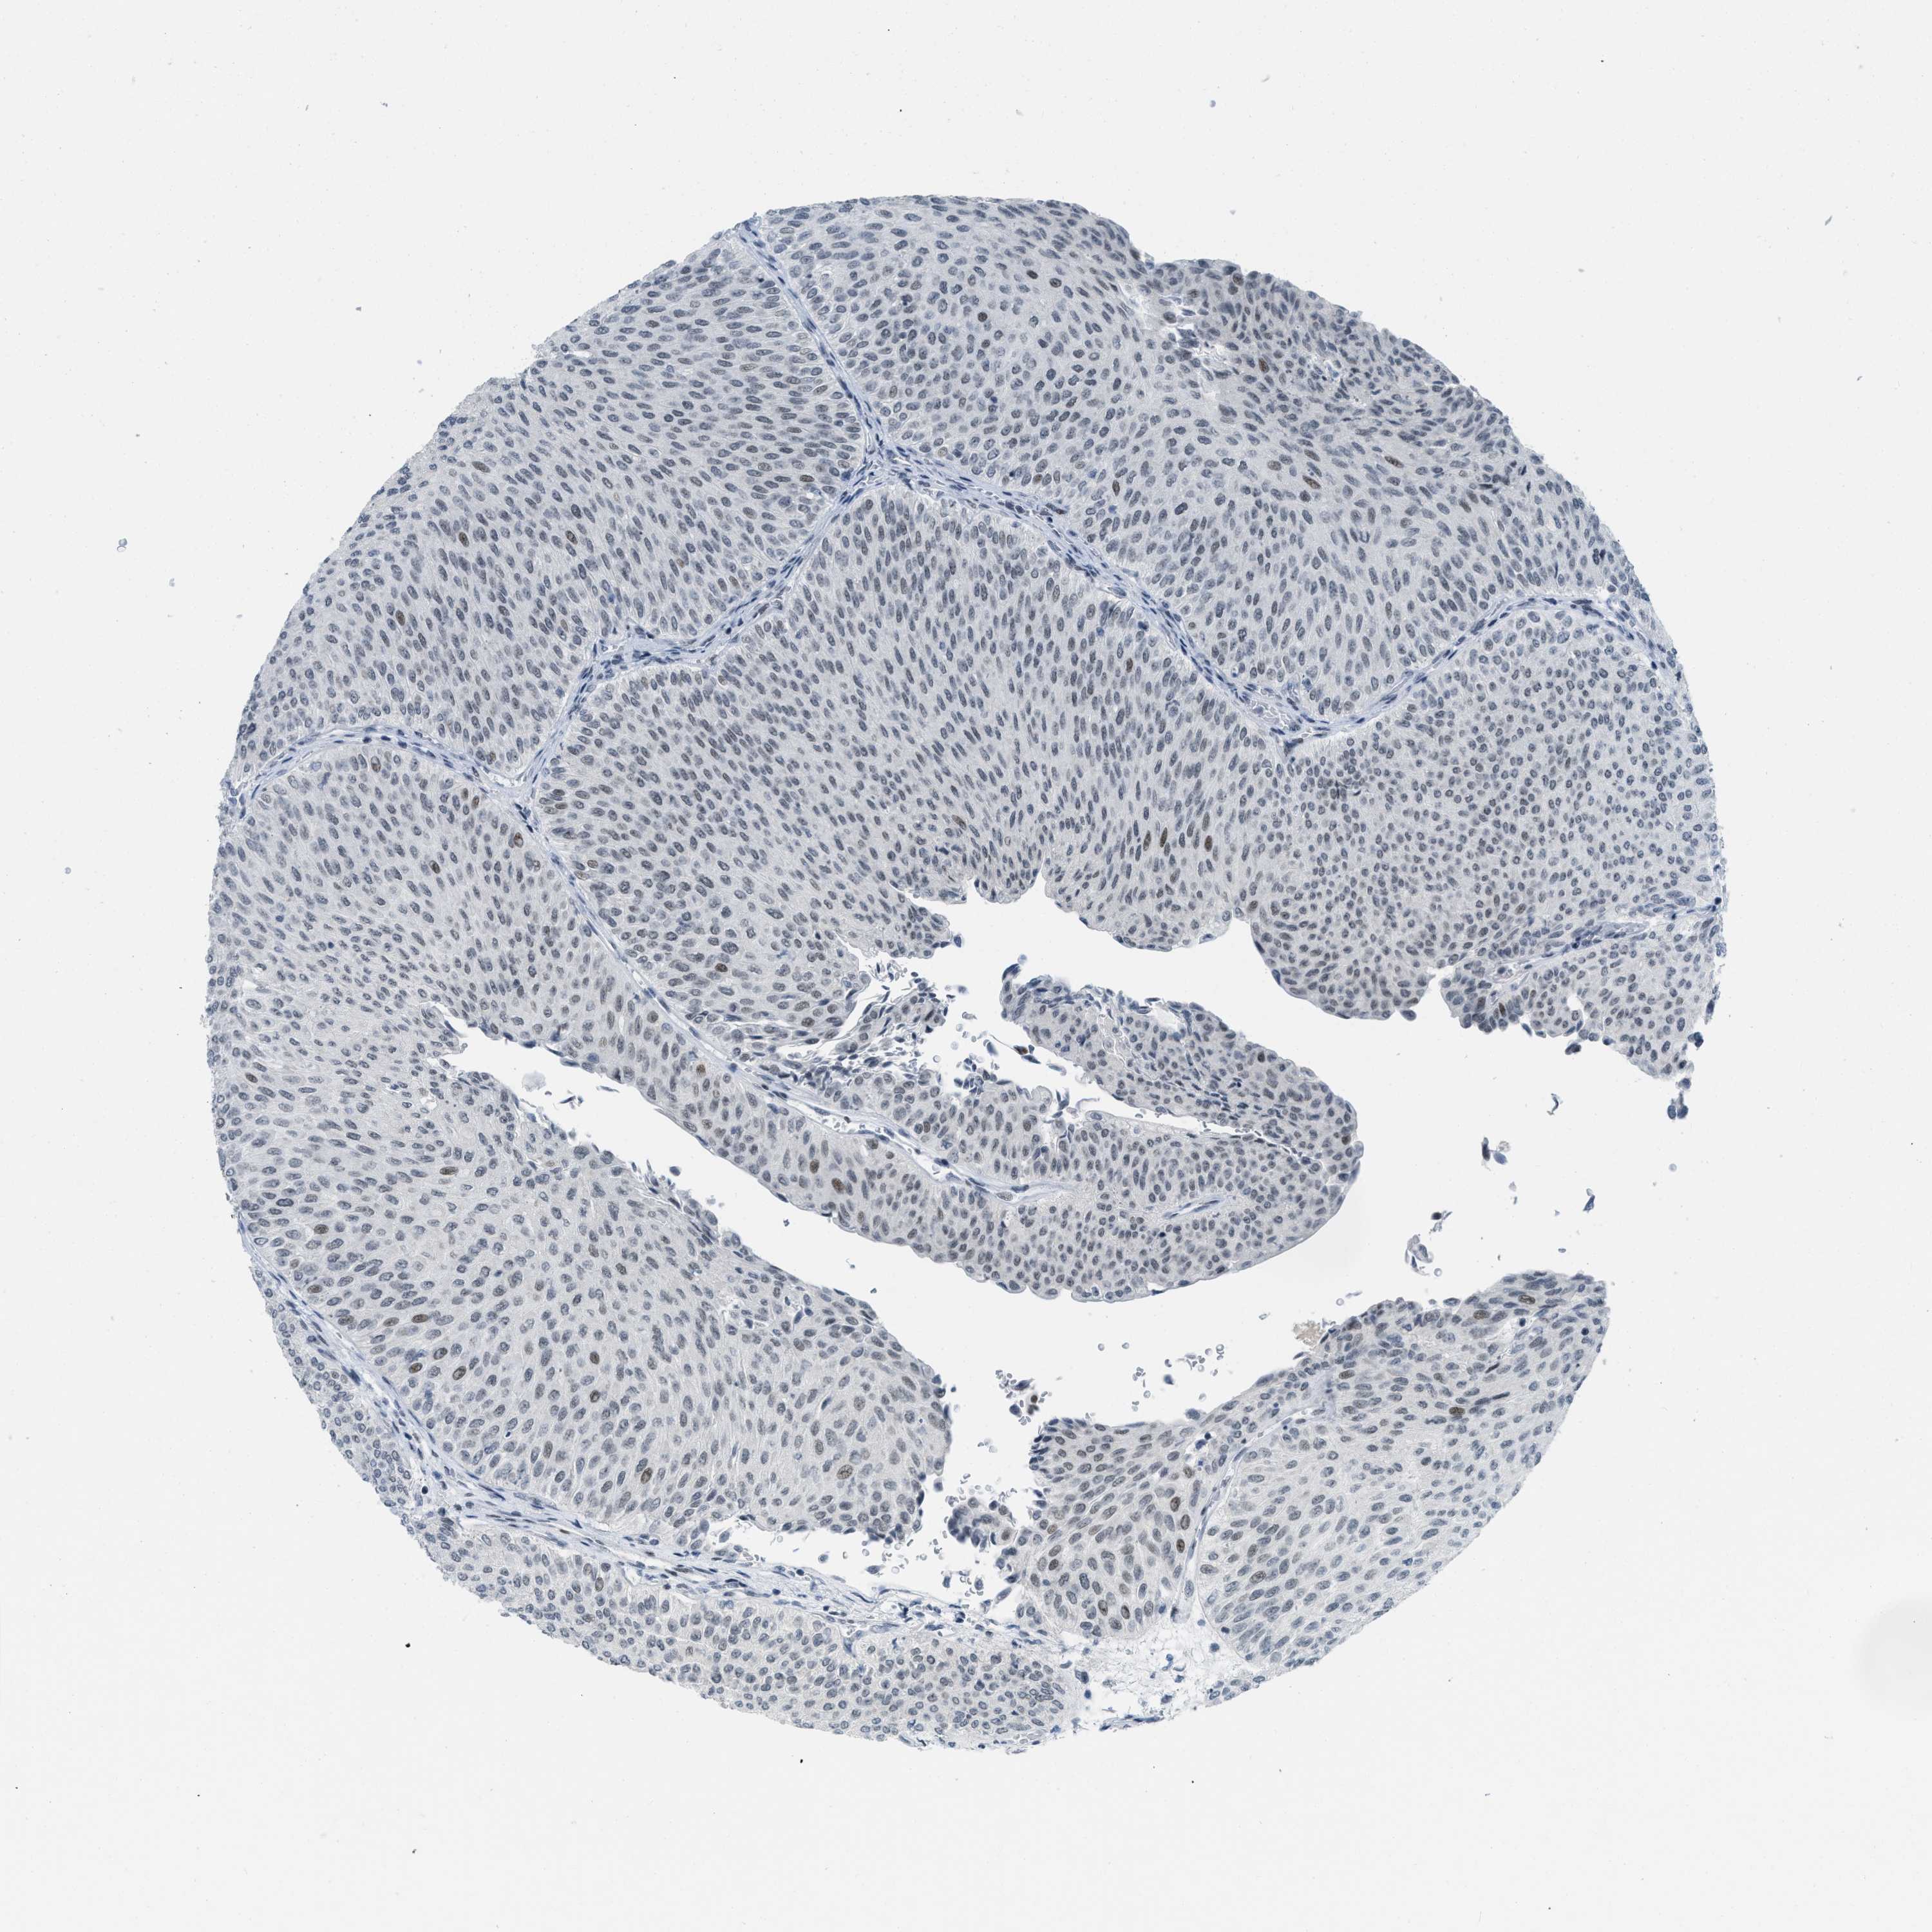

UROTHELIAL CANCER - Protein expressioni

A mouse-over function shows sample information and annotation data. Click on an image to view it in a full screen mode. Samples can be filtered based on level of antibody staining by selecting one or several of the following categories: high, medium, low and not detected. The assay and annotation is described here.

Antibody stainingi

Antibody staining in the annotated cell types in the current human tissue is reported as not detected, low, medium, or high, based on conventional immunohistochemistry profiling in selected tissues. This score is based on the combination of the staining intensity and fraction of stained cells.

Each image is clickable and will lead to virtual microscopy that enables deeper exploration of all samples and also displays staining intensity scores, fraction scores and subcellular localization as well as patient and tissue information for each sample.

Antibody HPA003505

Antibody HPA003881

Antibody CAB018768

Staining

High

Medium

Low

Not detected

Intensity

Strong

Moderate

Weak

Negative

Quantity

>75%

75%-25%

<25%

None

Location

Nuclear

Cytoplasmic/membranous

Cytoplasmic/membranous,nuclear

Urothelial carcinoma, High grade

Urothelial carcinoma, Low grade